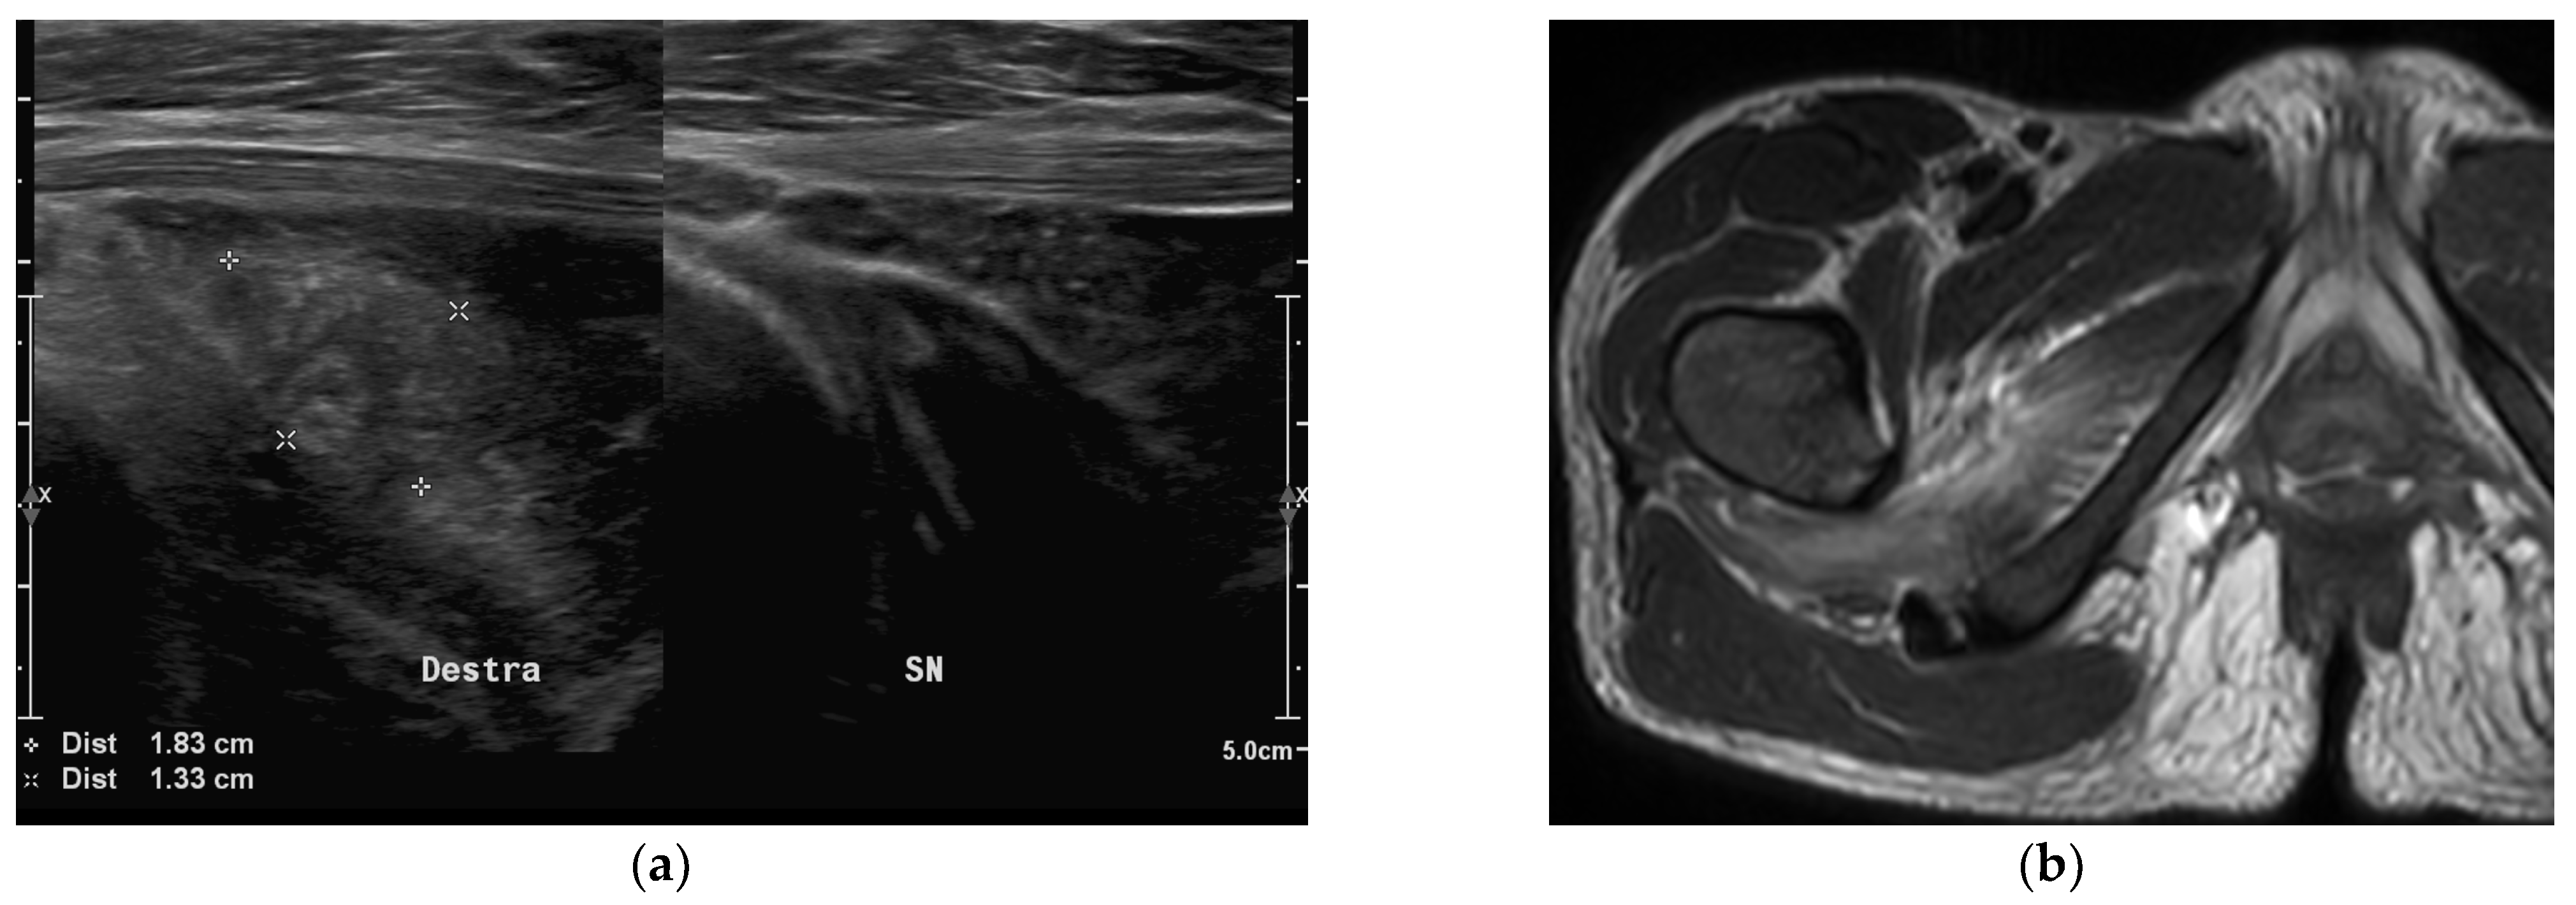

- Trusen, A.; Beissert, M.; Schultz, G.; Chittka, B.; Darge, K. Ultrasound and MRI features of pyomyositis in children. Eur. Radiol. 2003, 13, 1050–1055. [Google Scholar] [CrossRef]